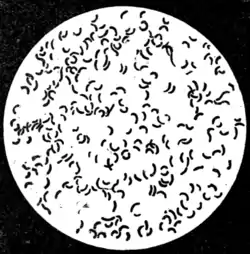

Description of the comma bacillus.—The comma bacillus (Fig. 77) is a very minute organism, 1.5 to 2 μ in length by 0·5 to 0·6 μ in diameter—about half the length and twice the thickness of the tubercle bacillus. It is generally slightly curved, like a comma; hence its name. After appropriate

Fig. 77.—Cholera bacillus. Agar culture: 24 hours' growth.

x 1,000. (Muir and Ritchie.)

staining, at each end, or at one end only, flagella can be distinguished—sometimes one, sometimes (though less frequently) two. These flagella, though of considerable length—from one to five times that of the body of the bacterium—owing to their extreme tenuity are difficult to see in ordinary preparations. They are not always present during the entire life of the parasite. In virtue of this appendage the bacillus exhibits very active spirillum-like movements. The individual bacilli when stained show darker parts at the ends or at the centre, suggesting spore formation. Sometimes in cultiva-